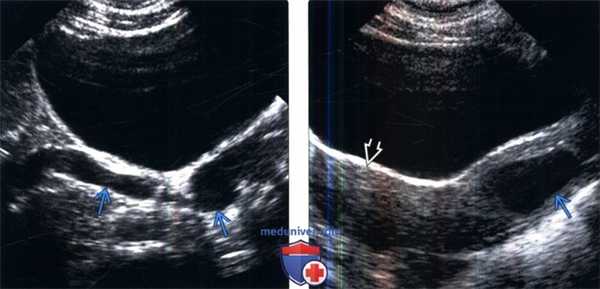

(Левый) На продольном ультразвуковом срезе удвоенной левой почки визуализируются диспластические кистозные изменения верхней лоханки.

(Правый) На поперечном ультразвуком срезе мочевого пузыря визуализируется расширенный левый мочеточник, который отходит от удвоенной левой почки, и прикрепляется с образованием крупного уретероцеле.

(Слева) УЗИ мочевого пузыря в продольной плоскости: извитой расширенный мочеточник, продолжающийся вне ожидаемого отверстия в треугольнике мочевого пузыря.

(Справа) УЗИ в продольной плоскости: у этого же пациента определяется кистозное образование в стенке влагалища, представляющее собой эктопическое устье расширенного и закупоренного мочеточника, дренирующего верхнюю лоханку удвоенной собирательной системы. Также визуализируется матка, которая имеет нормальные характеристики.

(Слева) УЗИ левой почки в продольной плоскости: расширенный эктопический мочеточник, медиальнее и глубже по отношению к почке. Следует обратить внимание на кистозную дисплазию части верхнего полюса.

(Справа) Микционная цистоуретерограмма: определяется рефлюкс мочи в эктопический левый мочеточник, который открывается в уретру.